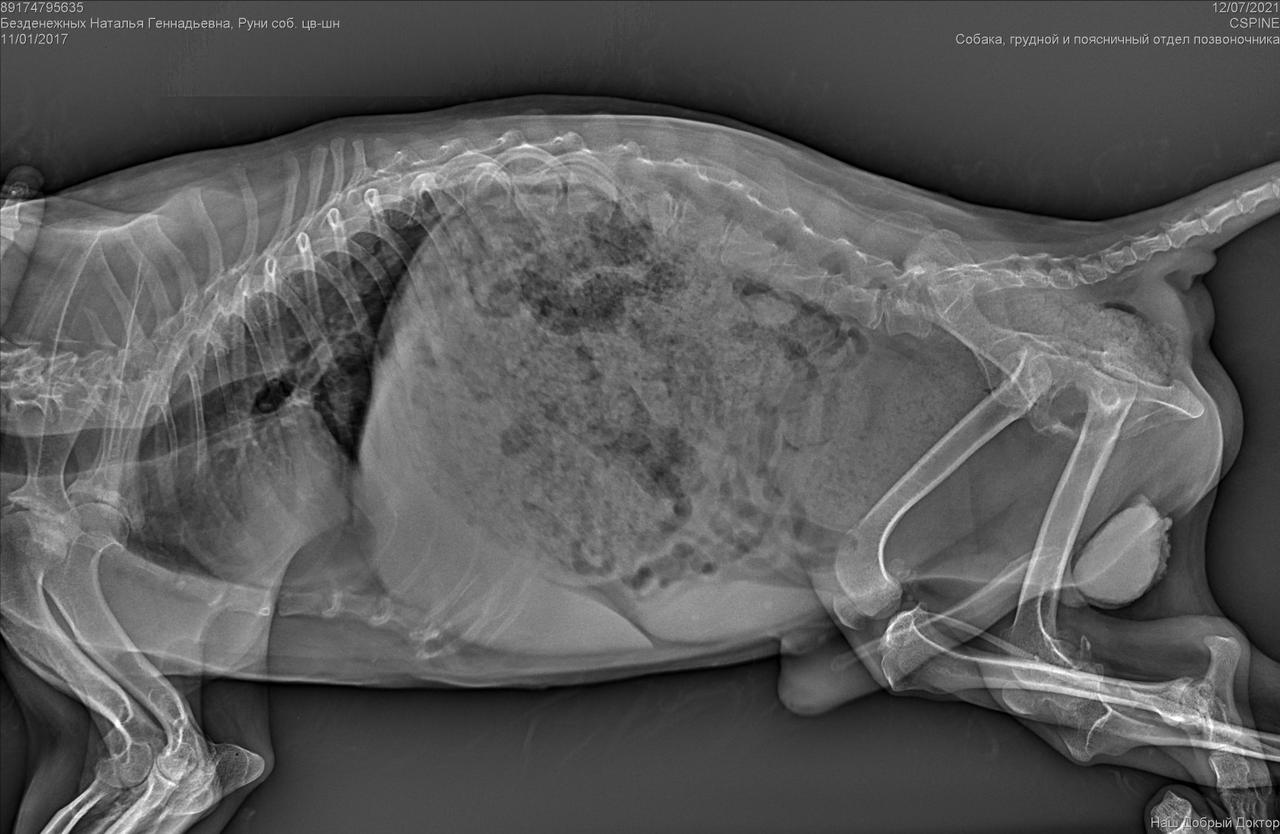

Клиника пообещала отправить рентген на электронку.

Рентген конечно.....

Была травма однозначно. Удалена головка бедра. Мышц нет.

И с позвоночником проблемы. Врачи говорят операции тут не помогут. Если только реабилитация , массаж. Восстановить как то мышцы